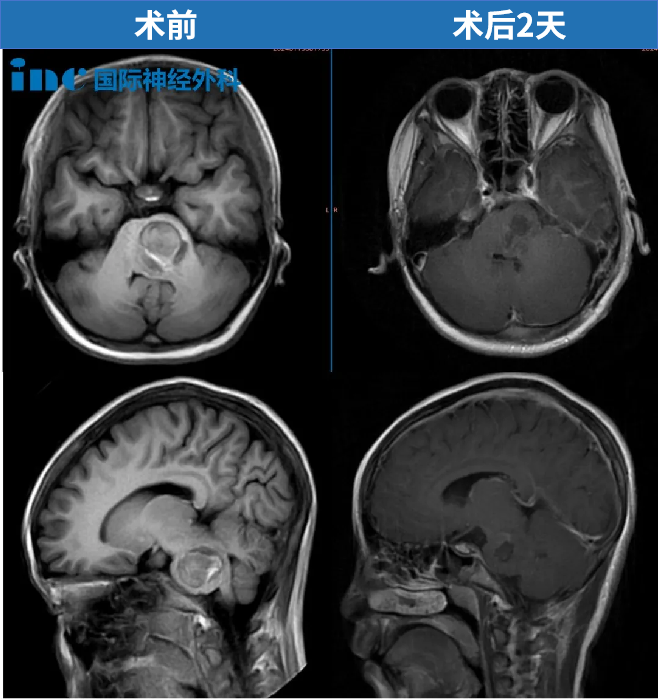

来看一个真实的紧急病例。12岁的女孩因出现类似流感症状就医,病情却在一天之内迅速恶化,最终发展为半身瘫痪,转入ICU抢救。影像检查确认:脑干海绵状血管瘤急性出血。120将她转诊至苏州大学附属儿童医院,由INC巴特朗菲教授主刀进行紧急手术,肿瘤顺利全切。

术后当天,女孩恢复了意识,能与家人正常交流;第二天即从ICU转入普通病房,肢体活动未受任何影响。术后两个月,她已经回到校园,生活一切如常。